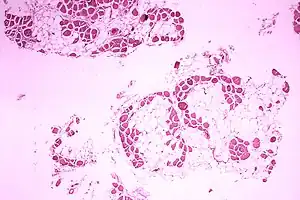

| Microscopic image of the calf muscle from a person with Duchenne muscular dystrophy. Cross section of muscle shows extensive replacement of muscle fibers by fat cells. | |

Muscle biopsy

If DNA testing fails to find the mutation, a muscle biopsy test may be performed.[20] A small sample of muscle tissue is extracted using a biopsy needle. The key tests performed on the biopsy sample for DMD are immunohistochemistry, immunocytochemistry, and immunoblotting for dystrophin, and should be interpreted by an experienced neuromuscular pathologist.[21] These tests provide information on the presence or absence of the protein. Absence of the protein is a positive test for DMD. Where dystrophin is present, the tests indicate the amount and molecular size of dystrophin, helping to distinguish DMD from milder dystrophinopathy phenotypes.[22] Over the past several years, DNA tests have been developed that detect more of the many mutations that cause the condition, and muscle biopsy is not required as often to confirm the presence of DMD.[23]